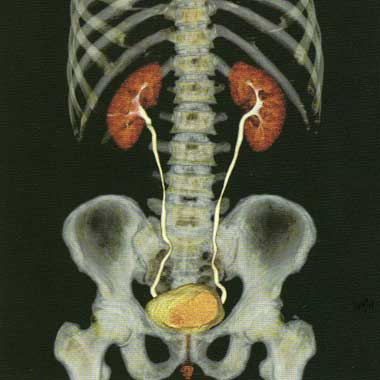

опухоли почек, мочевого пузыря на самых ранних стадиях; мочекаменная болезнь.

Все вышеизложенные методы диагностики проводятся с помощью Мультисрезового спирального компьютерного томографа Toshiba (Asteion Super 4) - 26 декабря 2006 года выпуска, который находится на базе 19-й городской больницы.

Аппарат Toshiba Astieon Super 4: относится к системе 3 поколения с непрерывным оборотом трубки и наиболее подходит для исследования головного мозга и всего тела включая исследования сердечно – сосудистой системы. Многосрезовая технология системы Asteion позволяет получать действительно изотропные объёмные данные. Эта технология позволяет расширить применение КТ и значительно увеличивает диапазон исследований.